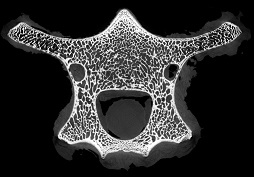

脊椎骨里的“笑臉表情包”

作者:ZZ 日期:2021-07-15 點擊數(shù):13359次

micro CT不僅能夠獲得整體骨量的變化,還能獲得骨骼內(nèi)部骨小梁骨微結(jié)構(gòu)的定量指標,進而將骨小梁微結(jié)構(gòu)指標、皮質(zhì)骨指標及骨量結(jié)合起來,綜合評價骨強度和骨量在骨質(zhì)疏松癥發(fā)生和發(fā)展中的作用。